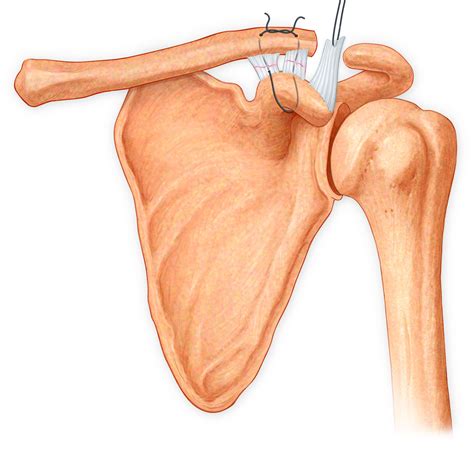

⚠️ Note: Always seek a professional physical exam or imaging (such as an MRI) if you suspect a Grade II or III tear, as these may require surgical intervention to restore stability.

• torn ligament in shoulder surgery